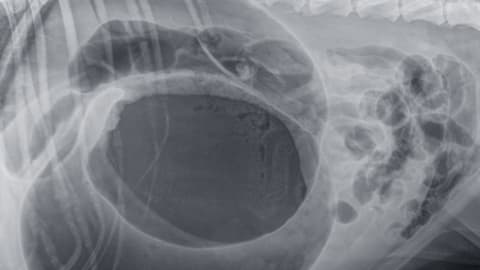

Mi is az a gyomorcsavar? A kutyák emésztőrendszeri vészhelyzete a gyomorcsavar, amely szaknyelven gyomortágulás és –csavarodás (GDV) néven ismert. Ekkor a gyomor...